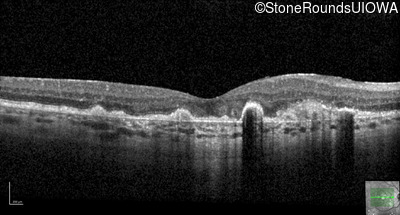

Malattia Leventinese (IIJ)

Malattia Leventinese (IIJ)

This 43 year old woman has experienced a gradual reduction in her central vision for the past 3 years.

| Malattia Leventinese | EFEMP1 | Arg345Trp CGG>TGG | AD |